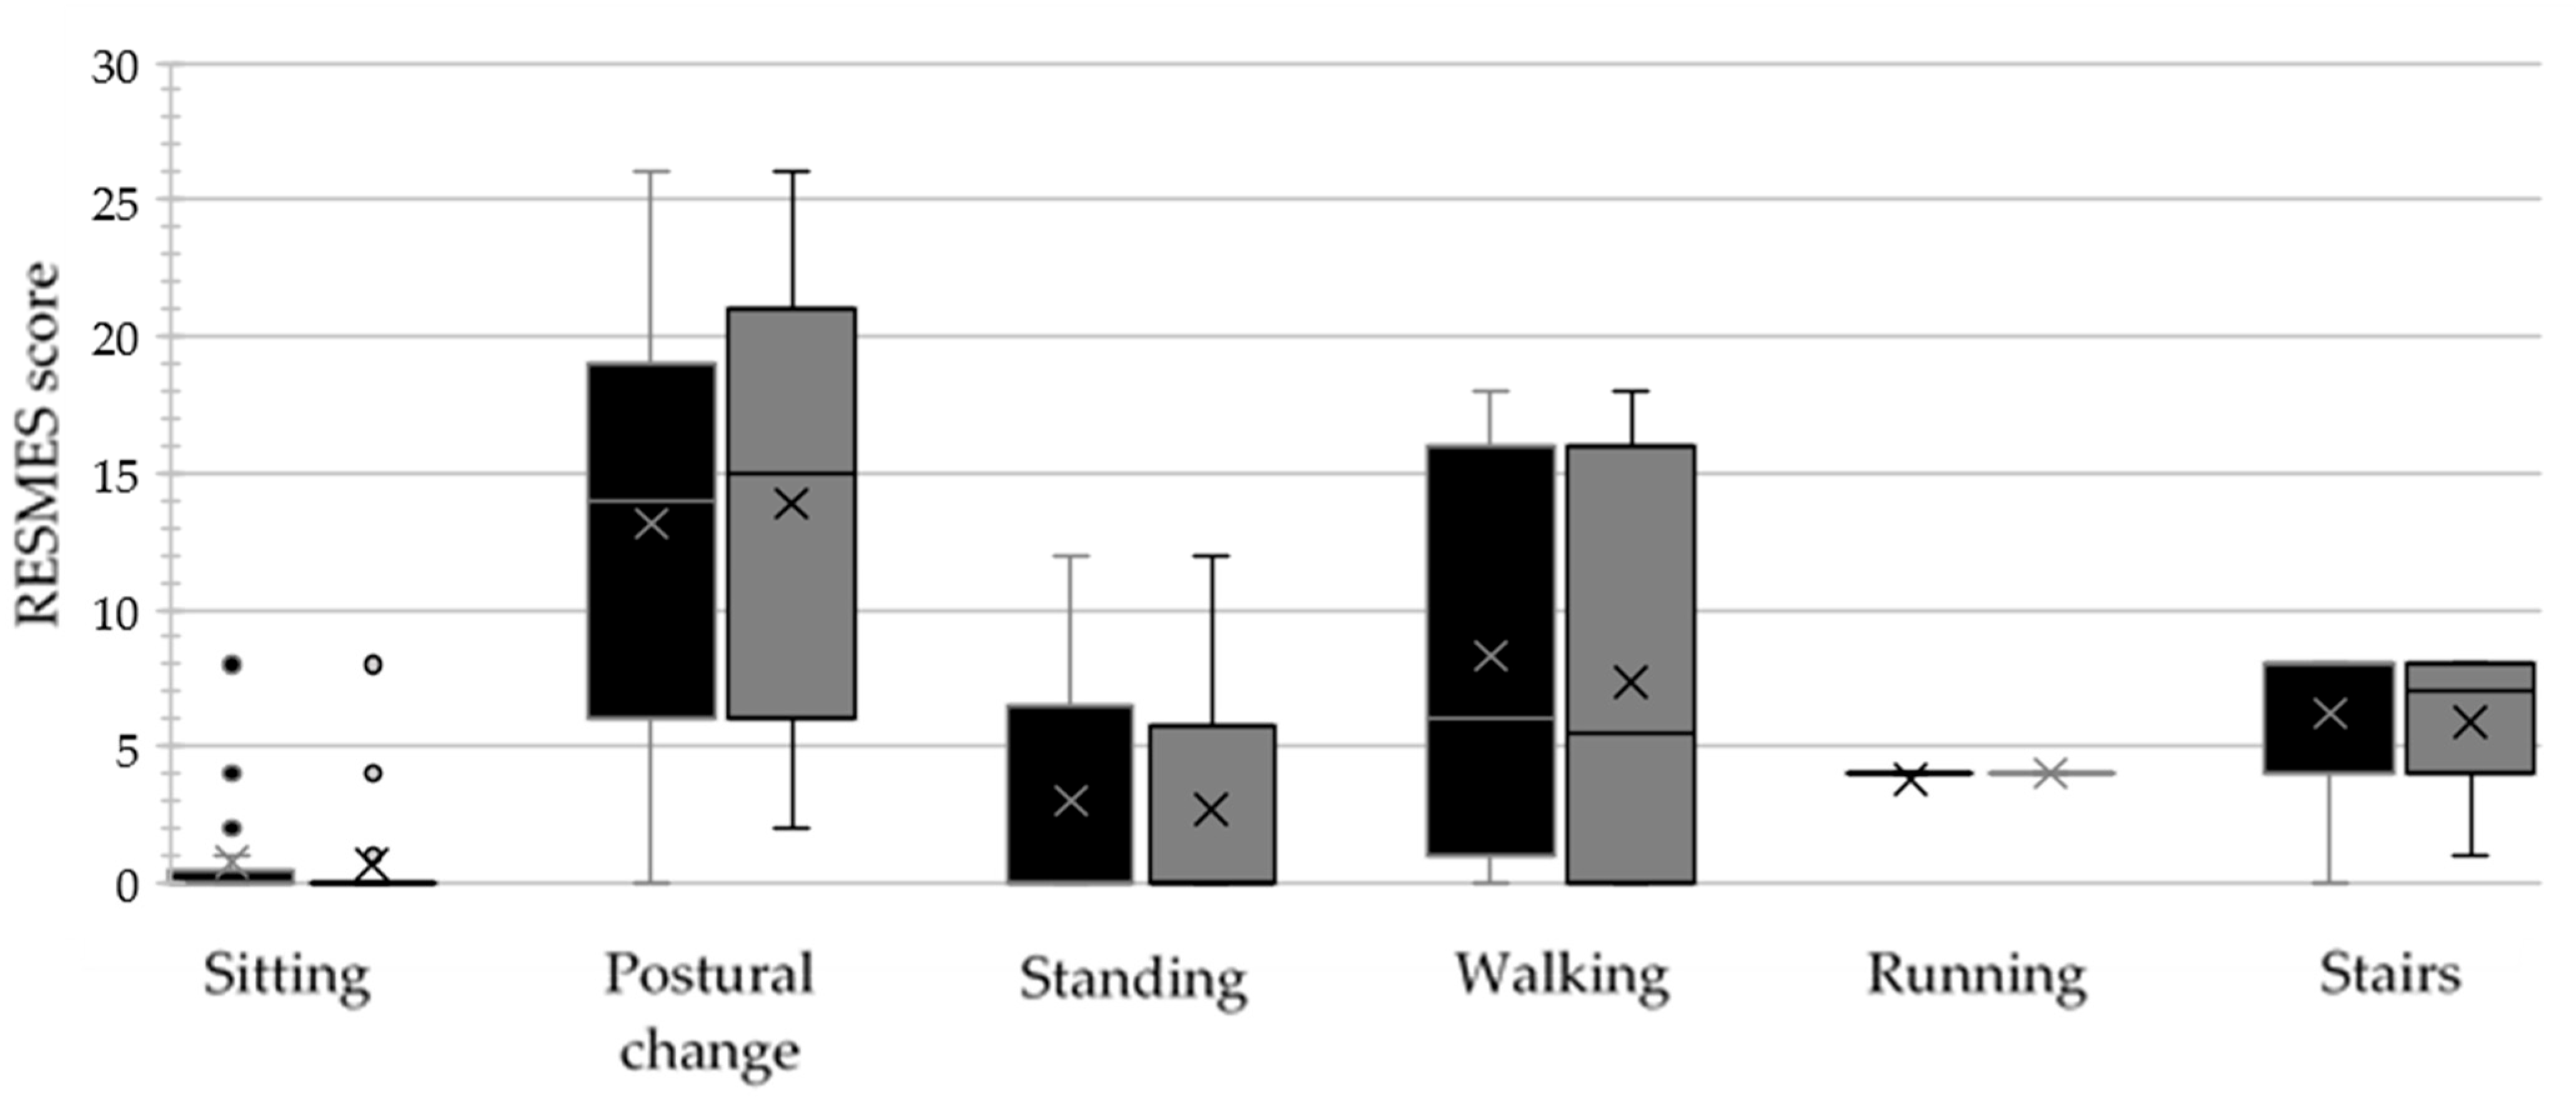

3.3. Gross Motor Function

4.2. Effect of the HEP on Gross Motor Function

| Subscale (Range) | Median (IQR) | p-Value (ES) | ||

|---|---|---|---|---|

| T1 | T2 | |||

| RESMES subscales | Sitting (0–12) | 0 (0.25) | 0 (0) | 0.424 |

| Postural change (0–28) | 14.5 (11.25) | 15 (12.75) | 0.669 | |

| Standing (0–12) | 0.5 (6.25) | 0 (5.25) | 0.026 | |

| Walking (0–18) | 8 (14) | 5.5 (16) | 0.009 | |

| Running (0–4) | 4 (0) | 4 (0) | 1.000 | |

| Stairs (0–8) | 8 (4) | 7 (4) | 0.021 | |

| RESMES total score (0–82) | 33.5 (37) | 31.5 (36.25) | 0.002 * (0.850) | |